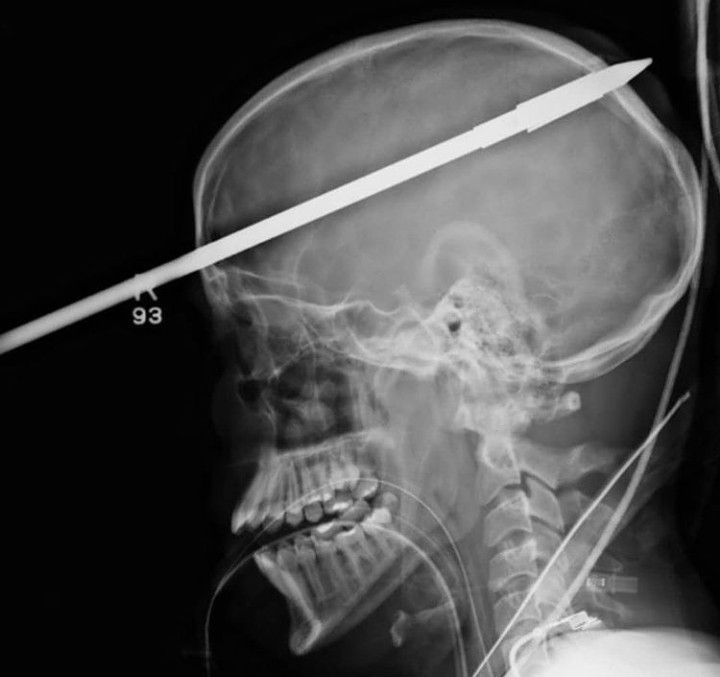

A 16-year-old survied an accident in which a spear gun his friend was holding accidentally discharged, causing a spear more than three-feet long to impale his skull and brain! Amazingly the teen survived, and was even able to speak to doctors throughout the whole ordeal. The spear is seen penetrating the front and back of the 16-year-old's skull. It entered the teen's head about two inches above the right eye. Doctors used a rebar cutter and locking pliers to stabilize the spear in the patient's head and remove 18 inches of the protruding spear from boy’s forehead to allow doctors to perform X-rays on the patient. Doctors needed to make sure none of the major blood vessels were injured so they performed an angiogram to take a picture of his blood flow to look for any problems. Miraculously there wasn't such damage. What's more, the right side of the brain where the injury occurred is considered "non-dominant" and doesn't control crucial areas such as cognition and speech. It also missed the deep seated structures in the brain. The spear was successfully removed in the operating room over a three-hour surgery and the doctors are optimistic about his recovery. By: https://www.instagram.com/p/CYhej7bIlcY/?utm_medium=copy_link